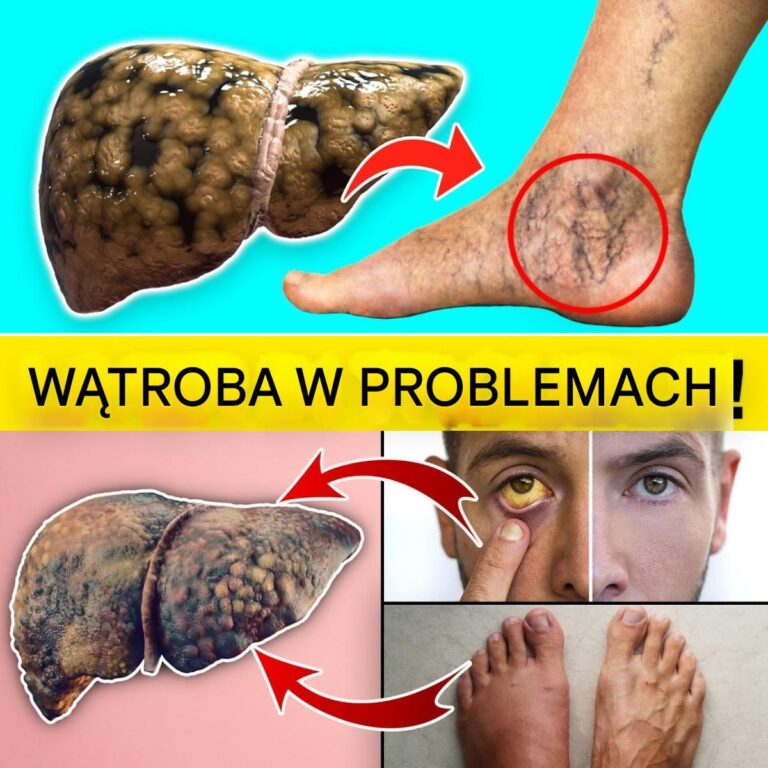

Twoja wątroba jest jednym z najciężej pracujących organów w twoim ciele — filtruje toksyny, wspomaga trawienie, równoważy hormony i magazynuje składniki odżywcze. Ale gdy…